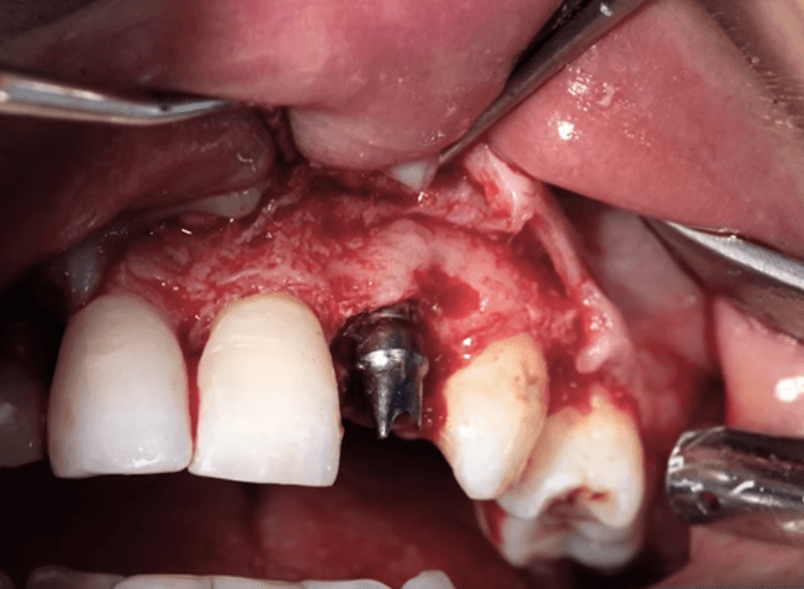

임플란트 주위염은 잇몸 손상과 임플란트 탈락을 유발할 수 있어 매우 주의가 필요합니다. 만약 주위염으로 인해 임플란트가 탈락한다면, 먼저 염증을 효과적으로 제거한 뒤 재식립을 진행해야 합니다. 그러나 재식립은 기존보다 더 높은 난이도와 복잡성을 요구하므로, 상태를 정확하게 체크하고 숙련된 의료진을 통해 체계적이고 섬세한 절차로 진행되어야 합니다.

임플란트는 현재로서 자연 치아를 대신할 수 있는 가장 효과적인 방법 중 하나로 인정받고 있습니다. 그러나 임플란트 주위염이 발생하면 임플란트를 제거하고 재식립하는 과정은 간단하지 않기 때문에 초기부터 신중한 관리가 필요합니다. 특히 정기적인 치과 검진이 매우 중요한데, 외부적으로는 문제가 없어 보이더라도 실제로 치조골이 손상되어 있는 경우가 있을 수 있습니다. 따라서 치과 전문의의 꾸준한 감독과 세심한 관리를 통해 임플란트가 오랜 기간 동안 튼튼하게 유지될 수 있도록 하는 것이 핵심입니다.